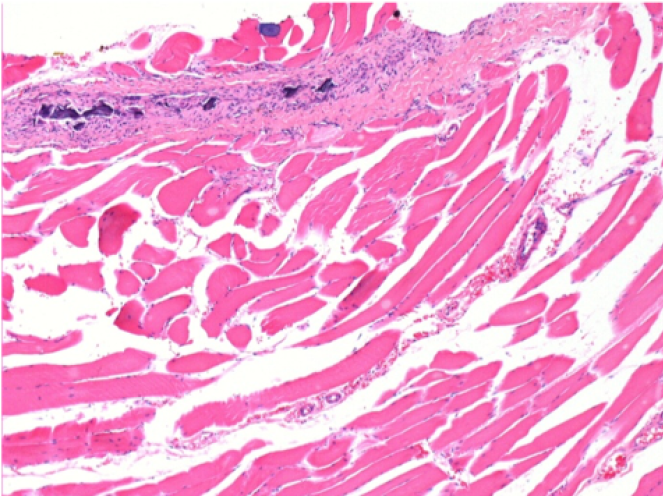

3 meses (D90) después de la inyección de Endopeel 0.1ml en el músculo pretibial derecho.

09